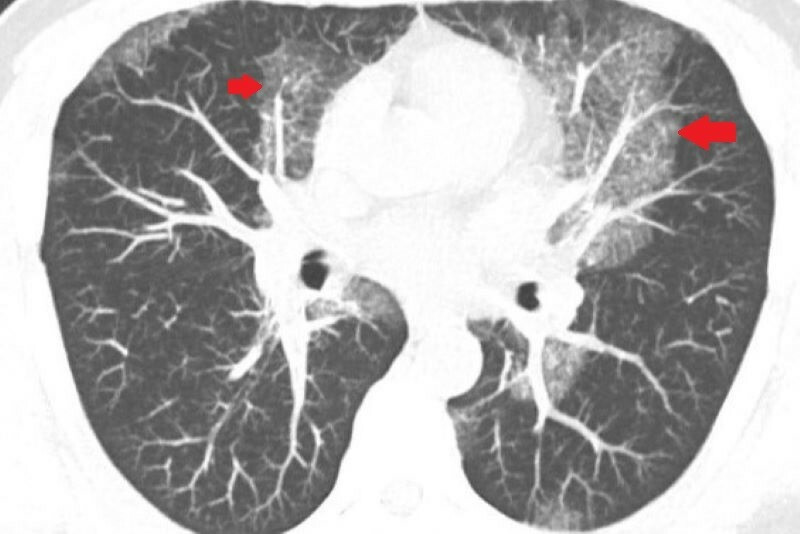

醫療團隊從電腦斷層初判魏先生為肺部慢性發炎,但透過支氣管鏡檢查顯示,氣道清晰無異常,細菌與黴菌等培養檢查也呈現陰性,病因成謎,只能密切追蹤病況,3個月後發現患者雙肺白影惡化,最後進行肺部穿刺切片,確診為極罕見的肺部蛋白質沉積症。

他表示,人在正常情況下,肺部會分泌表面張力素等蛋白質,協助肺泡維持張開、促進氣體交換,但當蛋白質異常累積,且無法被自然代謝清除,就會堵塞肺泡,導致缺氧、呼吸困難,嚴重時可能危及生命。此疾病早期常無明顯症狀,容易與肺炎、肺纖維化等疾病混淆,導致誤診與治療延誤。